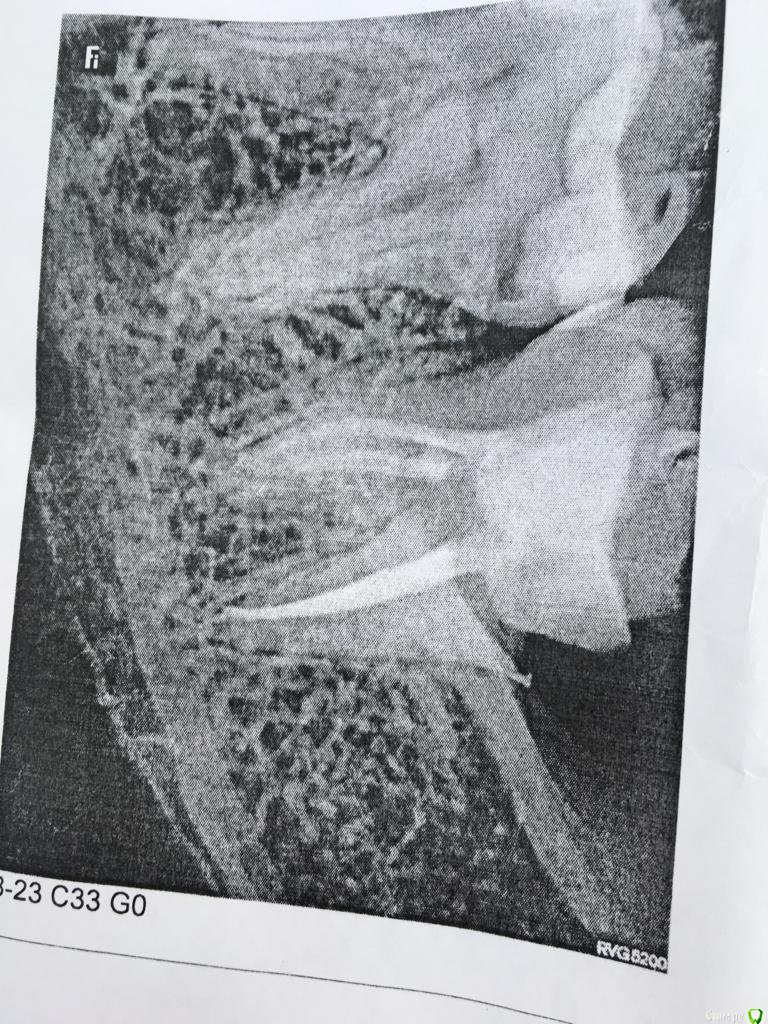

Роббоб Опубликовано 1 февраля, 2019 Автор Поделиться Опубликовано 1 февраля, 2019 Этот снимок сделан уже после похода к ортопеду. Вот снимок до. Был сделан неделю назад Ссылка на комментарий

Doc Опубликовано 1 февраля, 2019 Поделиться Опубликовано 1 февраля, 2019 Ну, если все под пломбой было, не временной, а постоянной, то можно и не лечить. Если был длительный контакт гуттаперчи в каналах со слюной, то лучше переделать. Ссылка на комментарий

Роббоб Опубликовано 1 февраля, 2019 Автор Поделиться Опубликовано 1 февраля, 2019 Зуб откололся сбоку и чуть сзади. Я так проходил месяца два. Но пломба как была на месте так и осталась. На последнем снимке вроде даже видно что со стороны десны отколото Ссылка на комментарий

DmitrySH Опубликовано 1 февраля, 2019 Поделиться Опубликовано 1 февраля, 2019 Если каналы были некоторое время разгерметизированы, то лучше сделать ревизию. Если герметично, то можно оставить. Это все можно понять при удалении пломбы Ссылка на комментарий

Роббоб Опубликовано 1 февраля, 2019 Автор Поделиться Опубликовано 1 февраля, 2019 (изменено) Если каналы были некоторое время разгерметизированы, то лучше сделать ревизию. Если герметично, то можно оставить. Это все можно понять при удалении пломбыРасскажу как все было. 25 января мне ортопед обточил зуб убрал пломбу и поставил времянку. В этот же день она благополучно слетела. Так я проходил до 31числа. 31 го числа меня осмотрел терапевт поставил снова времянку и отпустил с миром дальше заниматься коронкой. Много ли времени я проходил без пломбы? Изменено 1 февраля, 2019 пользователем Роббоб Ссылка на комментарий

DmitrySH Опубликовано 1 февраля, 2019 Поделиться Опубликовано 1 февраля, 2019 Если по правилам, то надо делать ревизию каналов. Но насколько сильно они там могут быть инфицированы, это не узнать. Даже на очном приеме. Ссылка на комментарий